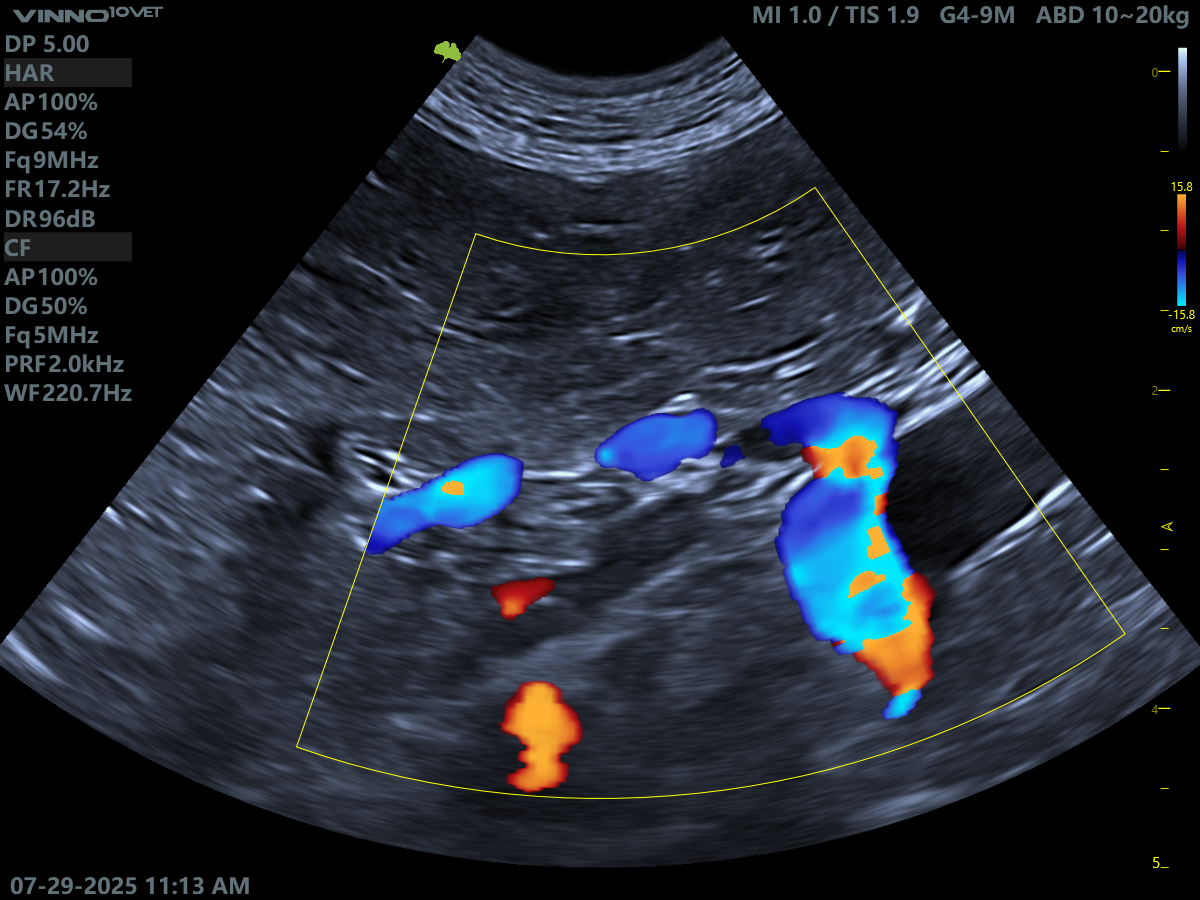

Image quality is excellent across all probes. The microconvex performs beautifully for abdominal scanning and even holds its own for basic cardiac work - making it a viable single-probe option if budget is tight. Just be aware that the microconvex probe doesn’t offer continuous wave Doppler. The linear probe gives crisp abdominal images (though it’s not a phased linear), and the phased array offers lovely cardiac imaging with high-quality Doppler.

Images from the D10